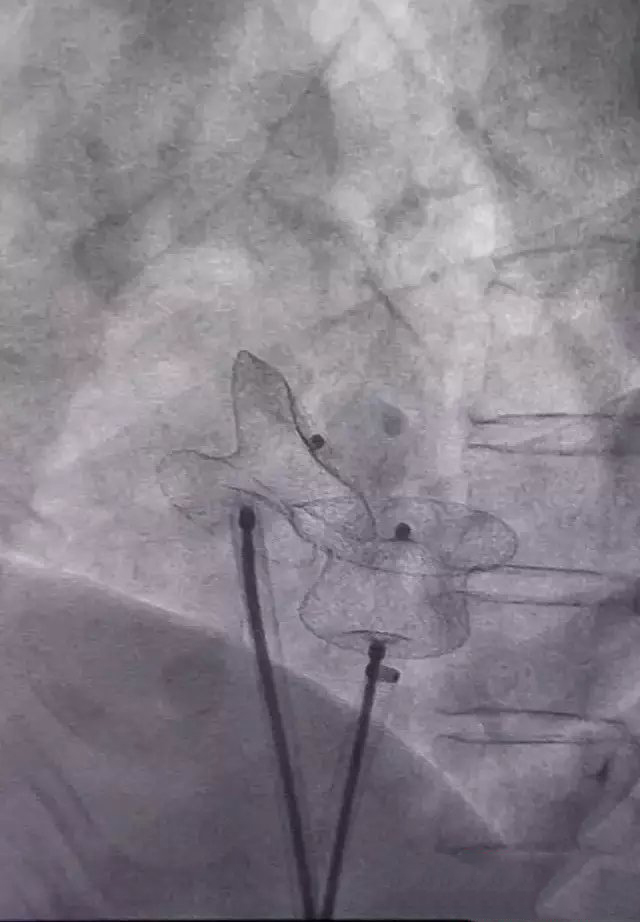

Recently, Xi'an Jiaotong University First Affiliated Hospital of structural heart diseases with Professor team using 3D printing technology, on the "atrial septal defect (holes: macroporous 19mm inferior small 12mm central type) patients using double occluder success, breaking the long inferior room septal defect can't do interventional treatment area.

After repeated communication with patients and their families, director Zhang founded the group therapy, according to the patients with transesophageal ultrasonography imaging and cardiac CT images, and Xi'an Jiaotong University 3D printing technology team collaboration, after repeated communication, repeated comparison and research are discussed and decided patients surgical plan, print out the 3D model of heart patients, for patients "tailored" to the appropriate type of occluder.

On August 10 in interventional operation room, with ultrasound room, with the director of the surgical team after 40 minutes is very successfully completed the surgery requires three hours to complete the operation in, and patients also awake to witness this. The operation completed successfully, marking the First Affiliated Hospital success broke the inferior atrial septal defect of the operation area, towards a new level of interventional therapy, is the first case in the country. The patient recovered well and was discharged from hospital after surgery.